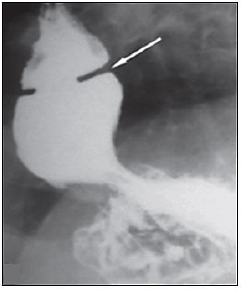

“Um paciente com diagnóstico de doença do refluxo gastroesofágico e queixa de disfagia realizou o seguinte exame contrastado do esôfago:”

Qual o diagnóstico mais provável?